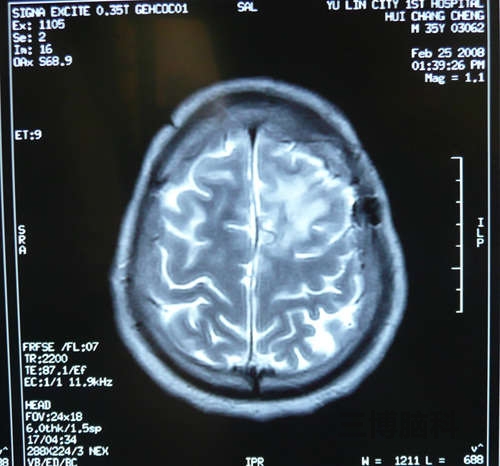

患者尹某,男,34岁。头痛、频发抽搐。MRI:左额顶近中先驱灶状占位,周围水肿明显。诊断:脑脓肿。立体定向微创技术切除病变。恢复良好。附图显示手术前后MRI比较。

术后显示:脑脓肿完全切除,患者症状消失,恢复良好。